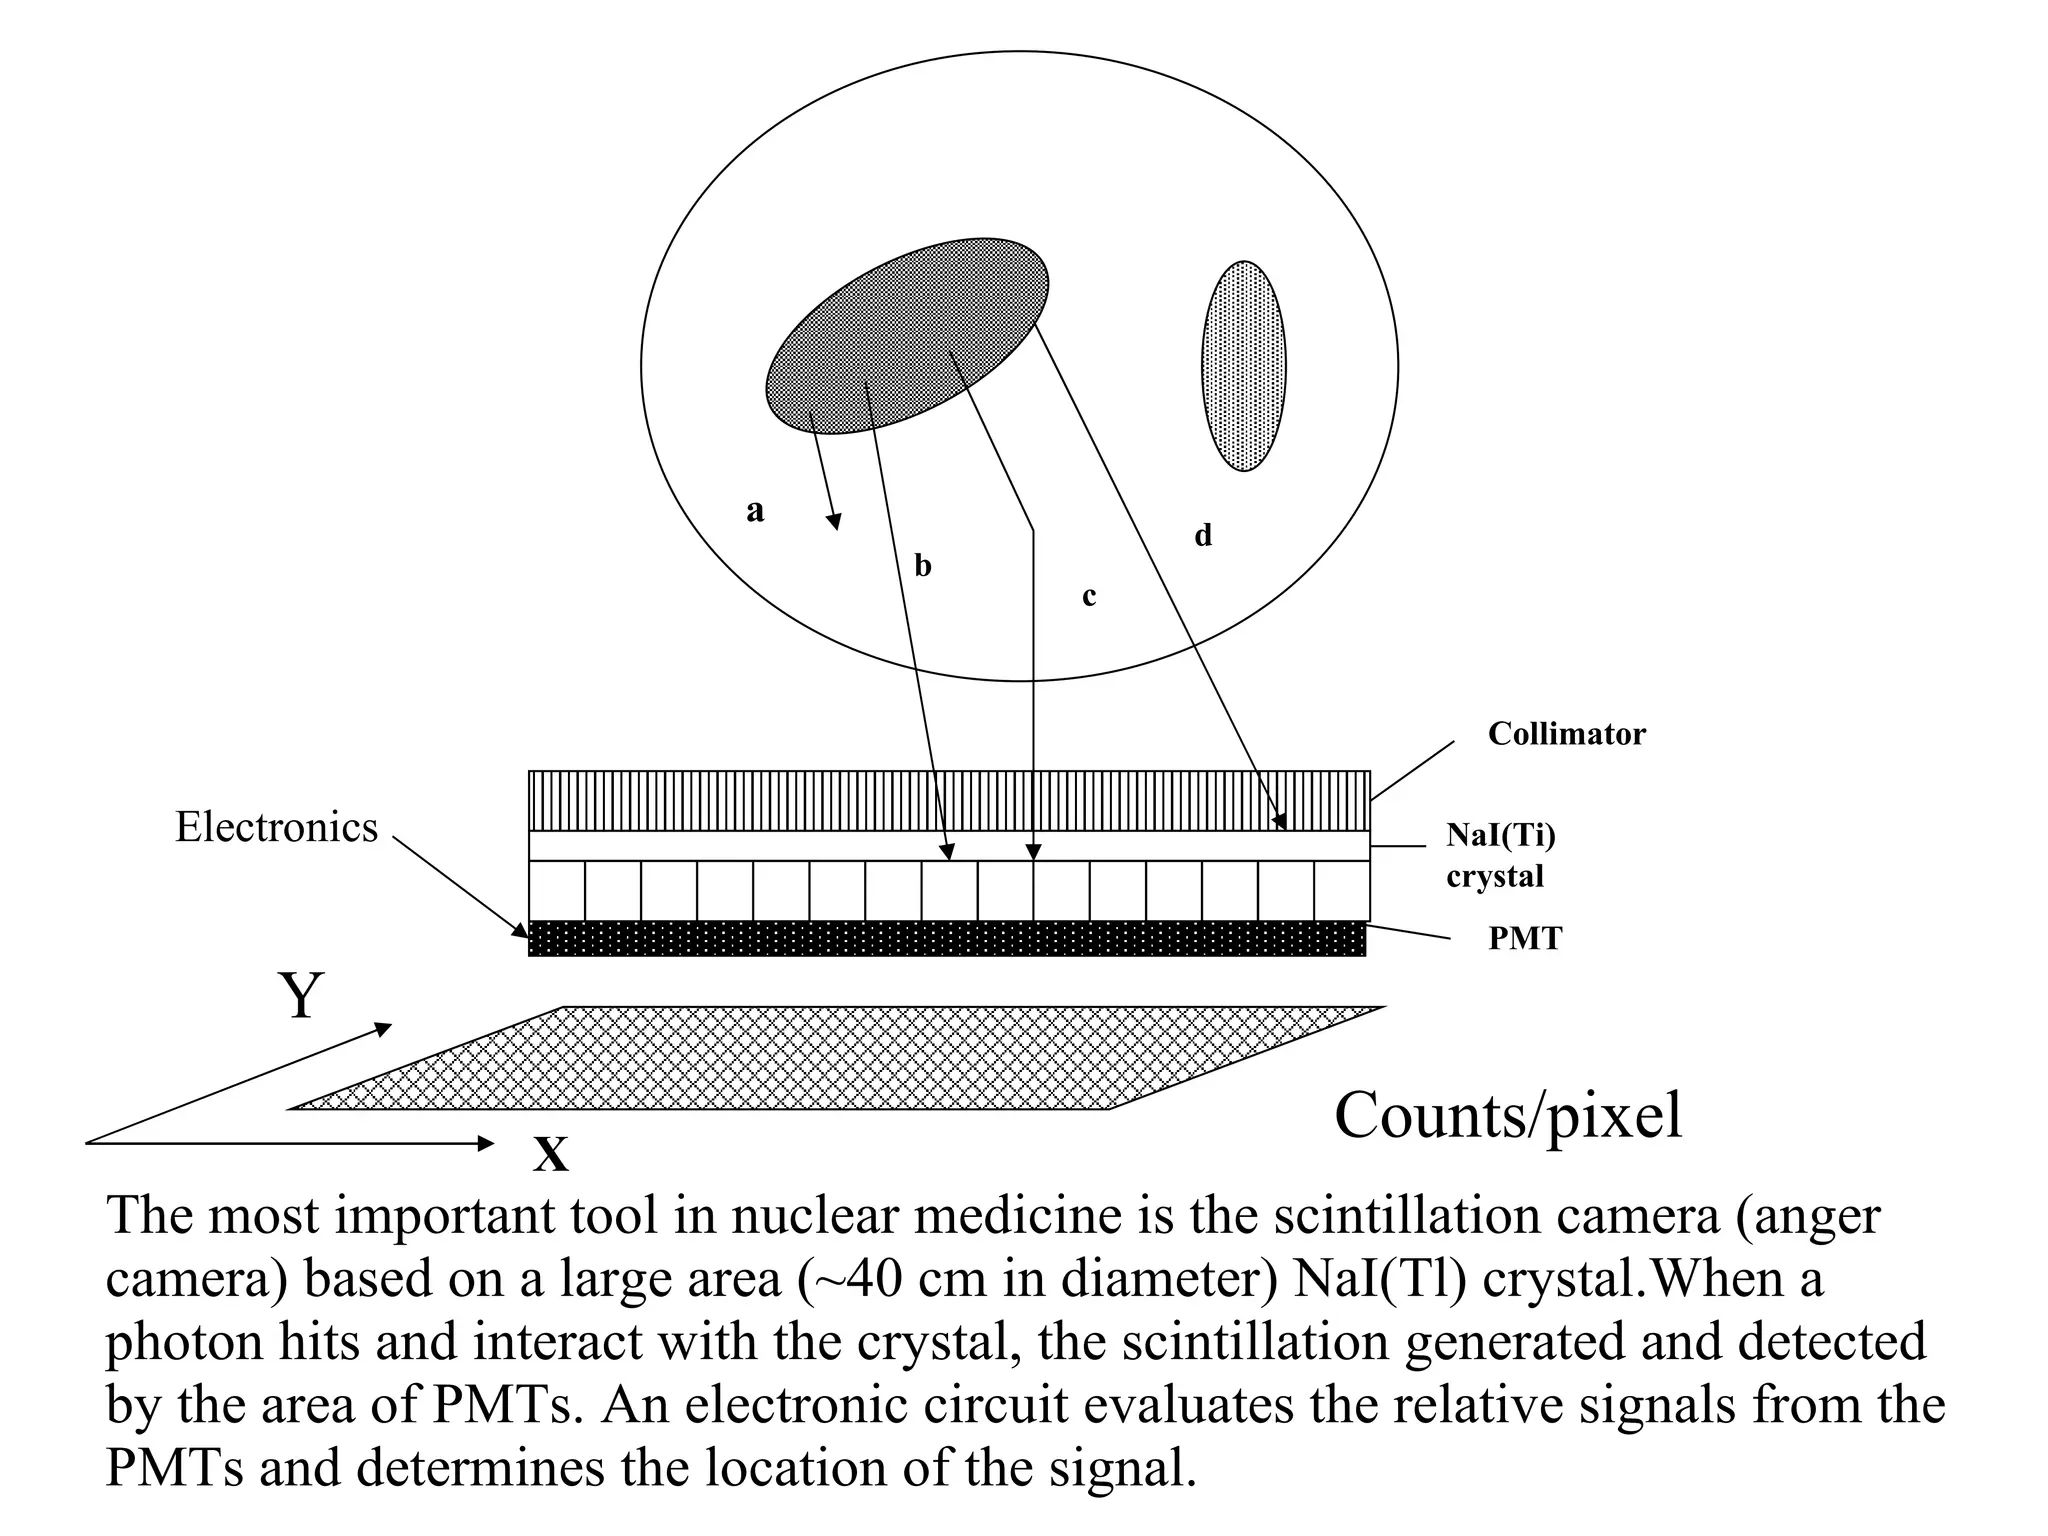

The document discusses various medical imaging modalities including x-rays, computed tomography (CT), and digital mammography. It describes the basic principles and historical development of these technologies, how images are formed, and what types of anatomical features and abnormalities they can detect. Key advances include the development of digital systems that allow image manipulation and remote consultation. While promising, digital mammography still faces challenges around resolution and cost.